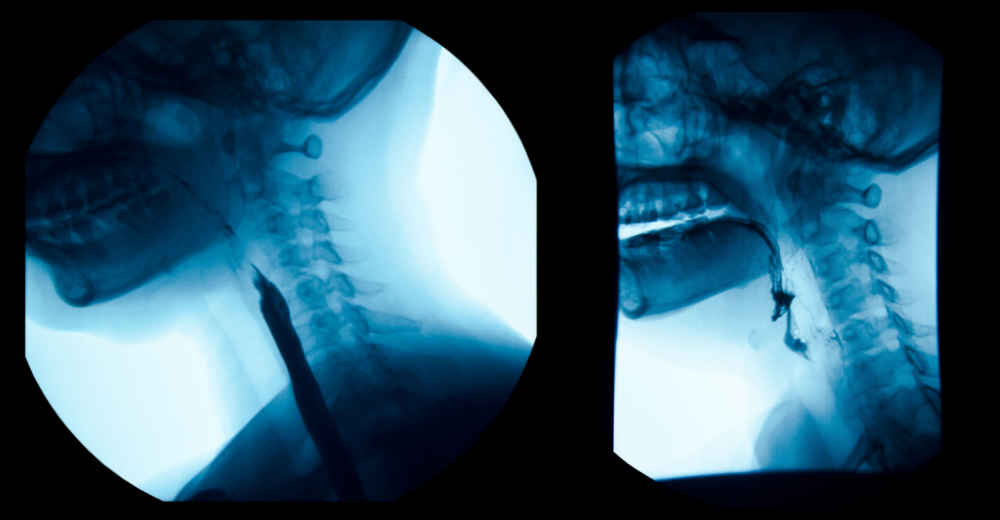

L’Esame RX Esofagogramma è un’indagine radiografica che sfrutta i raggi X combinati con un mezzo di contrasto a base di bario. Questo esame non invasivo permette di osservare la morfologia dell’esofago e di identificare eventuali anomalie o patologie. Presso il Poliambulatorio S-Medical Group di Sora, l’esame viene eseguito con tecnologie avanzate e da un team di esperti in grado di garantire sicurezza e accuratezza.

L’Esame RX Esofagogramma è una tecnica diagnostica che utilizza i raggi X per ottenere immagini radiografiche dell’esofago. Il termine “RX” si riferisce ai raggi X, mentre “Esofagogramma” indica l’immagine ottenuta. Questo esame è indicato per valutare il corretto funzionamento dell’esofago e per individuare eventuali patologie come stenosi, diverticoli, ulcere o tumori. È particolarmente utile per pazienti che presentano sintomi quali difficoltà nella deglutizione, reflusso gastroesofageo o dolore retrosternale.

Il paziente viene fatto accomodare su un lettino radiologico e gli viene somministrato un mezzo di contrasto a base di bario, che riveste le pareti interne dell’esofago. Successivamente, il paziente viene invitato ad assumere diverse posizioni per consentire l’acquisizione di immagini radiografiche complete da differenti angolazioni. Questo processo permette ai medici del Poliambulatorio S-Medical Group di Sora di ottenere una visione chiara e dettagliata della struttura dell’esofago e di rilevare qualsiasi anomalia presente.